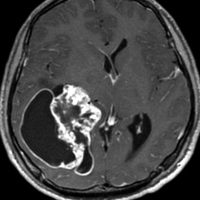

第4脳室床に発生した典型的な上衣腫 EPN-PFA の画像です。水頭症になって,頭痛と嘔吐,意識障害で発症しました。典型的なMRI画像と病理所見です。MRIでは第4脳室からマジャンディー孔を越えて脊髄背側まで長く腫瘍が伸びています。腫瘍内部に小さなのう胞が複数みられます。病理像では,血管周囲に細胞核がない無核野が認められます。血管周囲に伸びた繊細な単極性突起が集まった領域です。これは,血管周囲偽ロゼット perivascular pseudorosette という上衣腫に特徴的な病理所見です。

幼児の巨大な上衣腫です。左ルシュカ孔から延髄を取り囲む様に小脳延髄角槽に進展しています。最も典型的で治療が難しいタイプです。これはT2強調画像ですが,ガドリニウム増強されないものでした。

左が術前,右が術後です。脳底動脈の周囲が摘出できませんでした。幼児ですが手術後には局所照射をするしか方法がありません。

病理組織診断では退形成性上衣腫,MIB-1は40%以上にも達します。

この様なEPN-PFAは,脳外科の先生と小児科の先生が最も苦労するものですが,予後は極めて不良です。